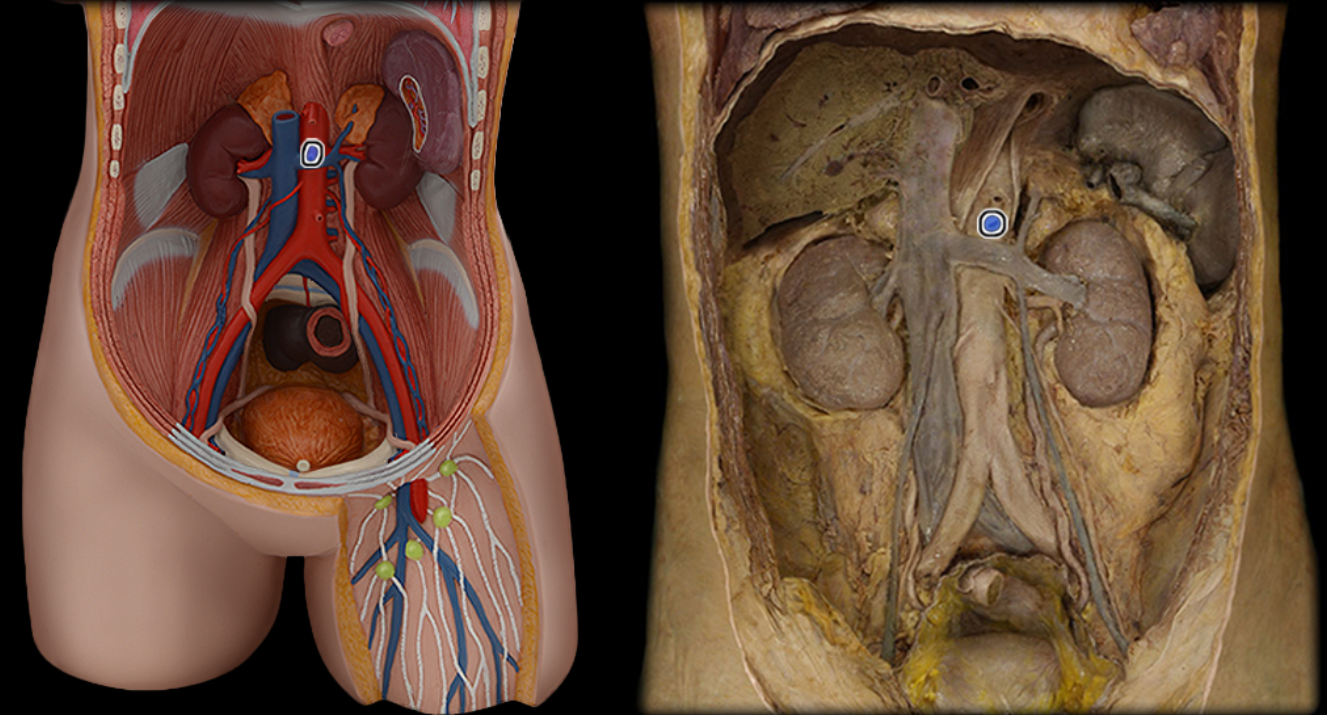

Abdominal aorta

Celiac a.

Common iliac a.

Common iliac v.

External iliac a.

External iliac v.

Femoral a.

Femoral v.

Gonadal a.

Gonadal v.

Great saphenous v.

Inferior mesenteric a.

Inferior vena cava

Lumbar a.

Lumbar v.

Renal a.

Renal v.

Superior mesenteric a.